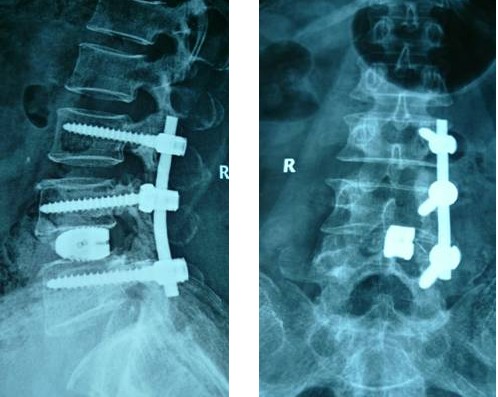

病例汇报2老年女性患者,因“反复腰腿痛10年、加重伴左下肢麻痛3年”之主诉入院,术前间断性跛行,左下肢肌力3+级,浅感觉减退。术后腰腿疼缓解,肌力及感觉恢复正常。(1、图2)

术后腰椎X线提示单侧钉棒系统固定稳妥,椎间隙高度恢复正常,融合良好。(图2